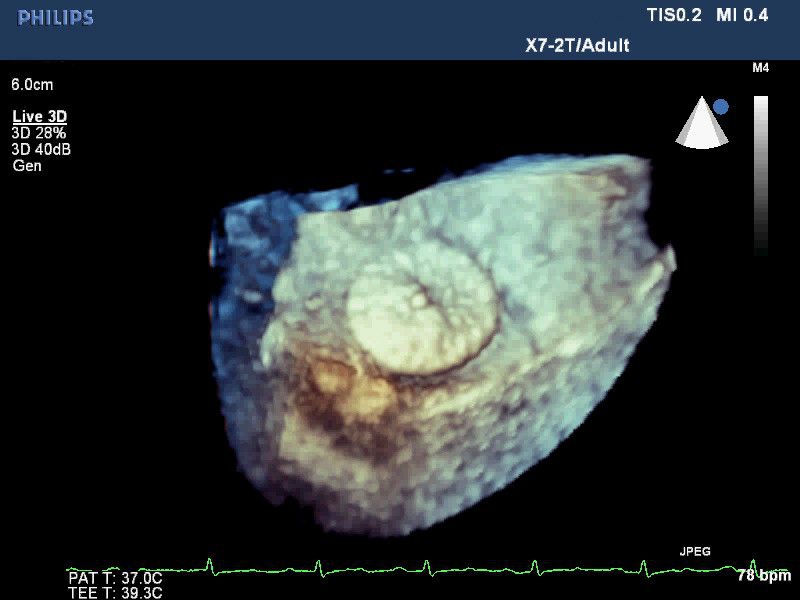

• Live 3D TEE: Эта функция позволяет проводить чреспищеводную эхокардиографию в режиме реального времени, что позволяет оценить механические сокращения сердца с точностью, необходимой для оценки результатов хирургического вмешательства.

• 3D эхо-кг в реальном времени (Live3DEcho): Эта технология позволяет получать объемные 3D изображения сердца в режиме реального времени.